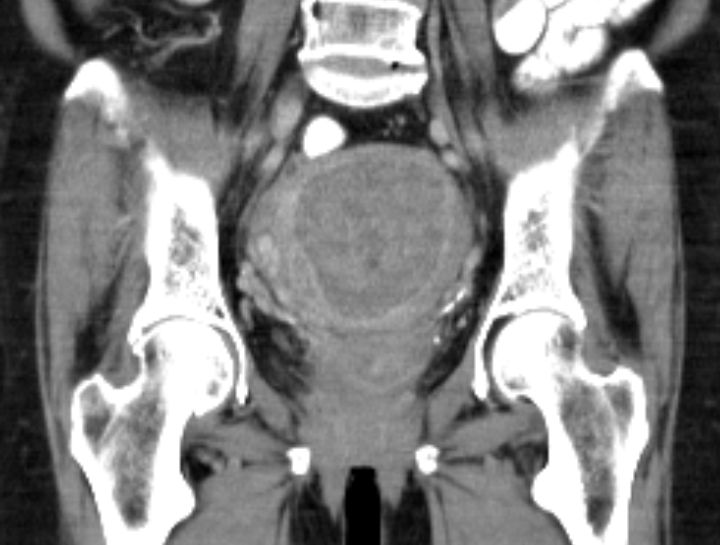

69-jährige Frau, die vor 4 Jahren ein Mammakarzinom hatte und adjuvant mit Anastrozol behandelt wird.

Wegen PM-Blutung wurde eine Abrasio durchgeführt, die einen malignen Müllerschen Mischtumor des Endometriums ergab.![]()  |

Postoperatives Stadium pT1a (beginnende Wandinfiltration) pNo Mo Lo Vo Ro![]()  | |